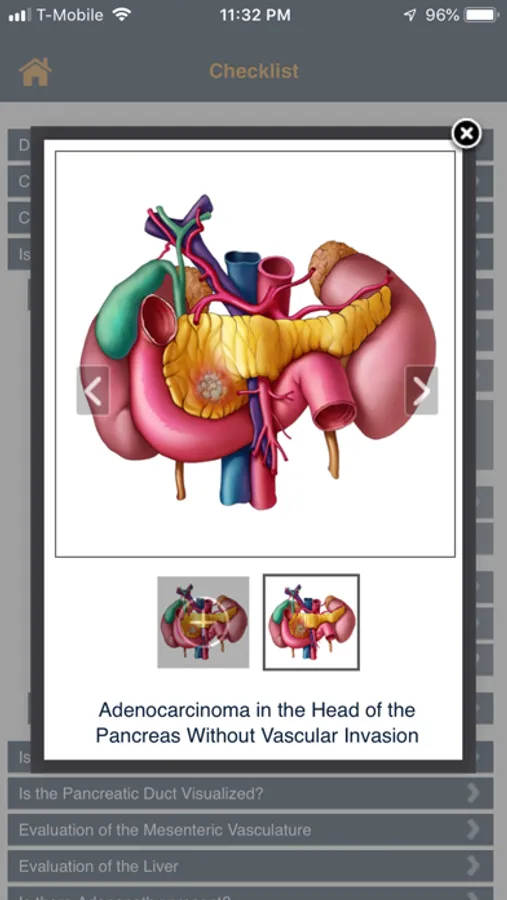

Checklists are a valuable tool when analyzing information and can be extremely valuable in the work flow of a medical professional. There are many factors that Radiologists must consider when evaluating and diagnosing the presence of a pancreatic tumor. The goal of the App is to provide a starting point for the systematic review of the CT scan of the patient with a suspected pancreatic mass. In this App there are a series of topics ranging from exam quality to patient age and sex to whether or not the common duct or pancreatic duct are dilated. Each topic is linked to additional topics or pearls which will help with the differential diagnosis and staging if a pancreatic tumor is present. After "hands on" experience with this program, the user will;